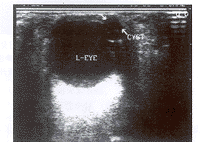

患者女,23岁。于3岁时由于外伤致双眼疼痛,视力骤减, 后右眼萎缩, 左眼视力逐渐恢复, 并常流泪。现患者自述,左眼胀, 眼球外突感10天来诊, 眼底镜观察发现瞳孔呈月牙形,用散瞳药后, 见瞳孔呈椭圆形。用BK2002ADI型彩超8.0MHz探头探查(用眼睑法):在左眼虹膜区可见一囊性肿物,大小约6.5mm×4.5mm, 边界清楚, 内部透声好, 囊肿壁极薄(图1),实时观察中, 见囊肿位置固定,能随着眼球转动而一致性移动。左眼的晶体、玻璃体、眼轴、球壁等均为正常回声,结合临床, 考虑为左眼虹膜囊肿, 患者后在外院手术治疗,证实为虹膜囊肿。

左眼前外侧有一小无回声区(CYST)

图 1 左眼长轴切面